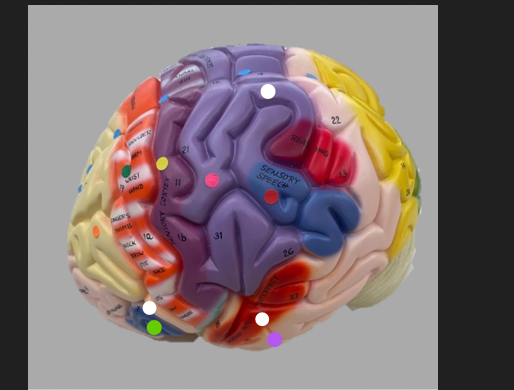

orange dot

frontal lobe

blue dot

longitudinal fissure

dark green dot

precentral gyrus

pink dot

postcentral gyrus

yellow dot

central sulcus

white dot

parietal lobe

light green dot

Broca’s Area

red dot

Wernicke’s Area

orange dot

occipital lobe

blue dot

parieto-occipital sulcus